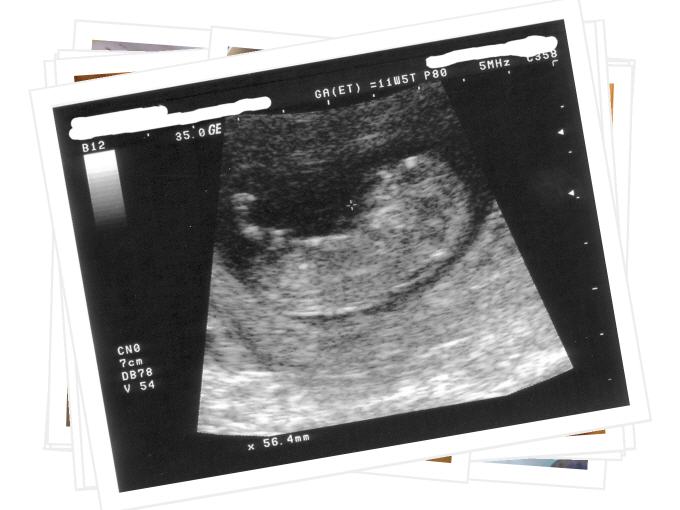

Geburtshilfe

Auf den folgenden Seiten können Sie sich einen Überblick über unser umfassendes Leistungsspektrum im Bereich Geburtshilfen und Pränataldiagnostik verschaffen.